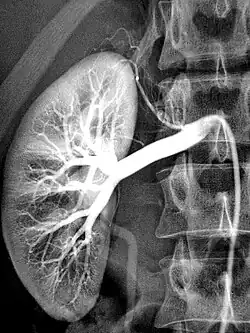

Die Bildgebung mit Röntgen-Kontrastmittel (KM) basiert darauf, dass diese die Röntgenstrahlen stärker absorbieren als die Umgebung. Im Wesentlichen wird dies durch den hohen Jodgehalt erreicht.[7] Daneben werden bariumsulfathaltige Suspensionen oder Xenon eingesetzt. Sie verbessern die Darstellung von Strukturen und Funktionen des Körpers bei bildgebenden Verfahren wie Röntgendiagnostik, Magnetresonanztomographie (MRT) und Sonografie (Ultraschall). Prinzipiell kann jede Arterie zu diesem Zwecke punktiert und einer Injektion unterzogen werden.

Arteriografie einer gesunden Niere